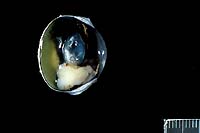

- Case 12-3. Eye. As described below.

- Gross Pathology: An irregularly shaped, pale tan mass

measuring approximately 0.75 cm in diameter was present within

- Contributor's Diagnosis and Comments: Eye: Iridociliary

- A partially encapsulated, highly cellular mass consisting

of cuboidal to polygonal cells arranged in loose cords, packets,

and occasional rosettes is adherent to the posterior aspect of

the iris and to the ciliary body. The neoplasm infiltrates the

base of the iris and extends into the filtration angle. Irregularly

shaped, dilated channels are present in some areas, and the mass

is supported by a fine fibrovascular stroma. Cells within the

mass have large, round to oval, occasionally indented nuclei,

1-2 nucleoli, finely stippled chromatin, small to moderate amount

of foamy, eosinophilic cytoplasm, and variably-distinct to indistinct

cell margins. A few cells have large, irregularly shaped nuclei,

and the mitotic rate varies from 0-3 per high-powered field.

Some scleral vessels adjacent to the neoplasm contain thrombi

and seemingly have "infiltrates" of cells (may not

be visible in all sections); the cells are dissimilar to those

within the neoplasm and may, in fact, represent a reaction to

thrombosis or other negative vascular events.

- Case 12-3. Eye. A monomorphic mass replaces the iris.

- Case 12-3. Ocular tumor. Sheets of pleomorphic polygonal

cells occasionally palisade around a central lumen (pseudorosette

formation).